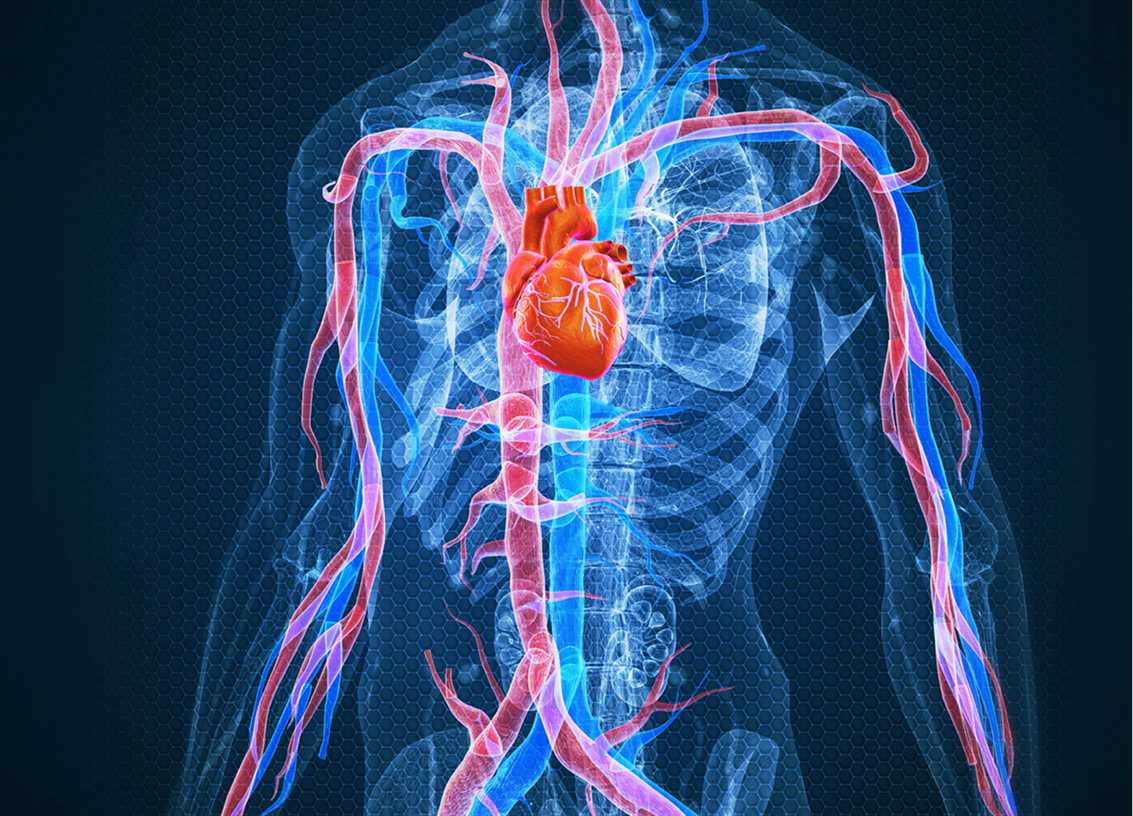

When you don't get enough sleep, your body lacks the downtime it needs to regulate different functions and organs, including your heart, blood vessels, and overall circulatory health. Long-term effects of insomnia can include:

During normal, healthy sleep, your blood pressure drops. This “nocturnal dipping” is important for good heart health, and a lack of sleep can prevent this dip. This may raise your risk of hypertension, or high blood pressure. Hypertension puts extra strain on your heart and blood vessels and is associated with higher risks of heart disease and stroke.

Studies have shown that people with chronic insomnia are more likely to develop heart disease. Being sleep deprived can lead to inflammation and plaque buildup in the arteries. Over time, this narrows the arteries, making it more difficult for blood to flow and elevating the risk of heart diseases, including heart attacks.